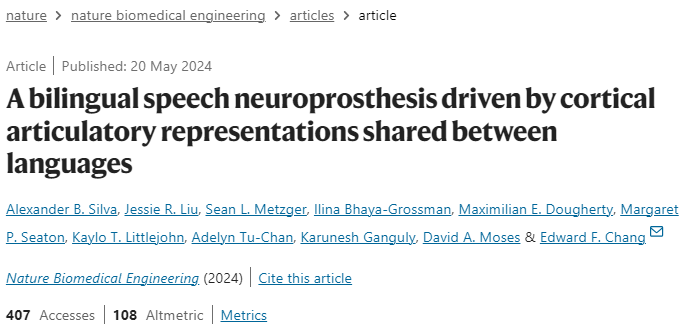

这项研究的参与者,绰号"Pancho(潘乔)",20岁时因中风导致身体大部分瘫痪。因此,他只能发出呻吟和咕哝声,却不能清楚地说话。30多岁时,潘乔与加州大学旧金山分校(University of California, San Francisco)的神经外科医生爱德华·张(Edward Chang)合作,研究中风对他大脑的持久影响。在2012年发表的一项开创性研究中,Chang的团队通过手术将电极植入Pancho的皮层,以记录神经活动,并将其转化为屏幕上的文字。

为了实现这一目标,由Chang的博士生Alexander Silva领导的这项工作开发了一个人工智能系统来破译潘乔的双语语音,包括在Pancho试图说出近200个单词时训练系统。他拼单词的努力创造了一个独特的神经模式,并被电极记录下来。

然后,作者将他们的人工智能系统(包括一个西班牙语模块和一个英语模块)应用于潘乔尝试大声说出的短语。对于短语中的第一个单词,西班牙语模块会选择与神经模式最匹配的西班牙语单词。英语模块也会这样做,但会从英语词汇中进行选择。例如,英语模块可能会选择"she "作为短语中最有可能出现的第一个单词,并评估其正确概率为 70%,而西班牙语模块可能选择“estar”(to be),并评估其正确的概率为40%。

从那里,两个模块试图建立一个短语。他们每个人都选择第二个单词,不仅基于神经模式的匹配,而且还基于它是否可能跟随第一个单词。因此,"I am"会比"I not"获得更高的概率得分。最后输出两个句子——一个用英语,一个用西班牙语——但是Pancho面对的显示屏只显示总概率得分最高的版本。